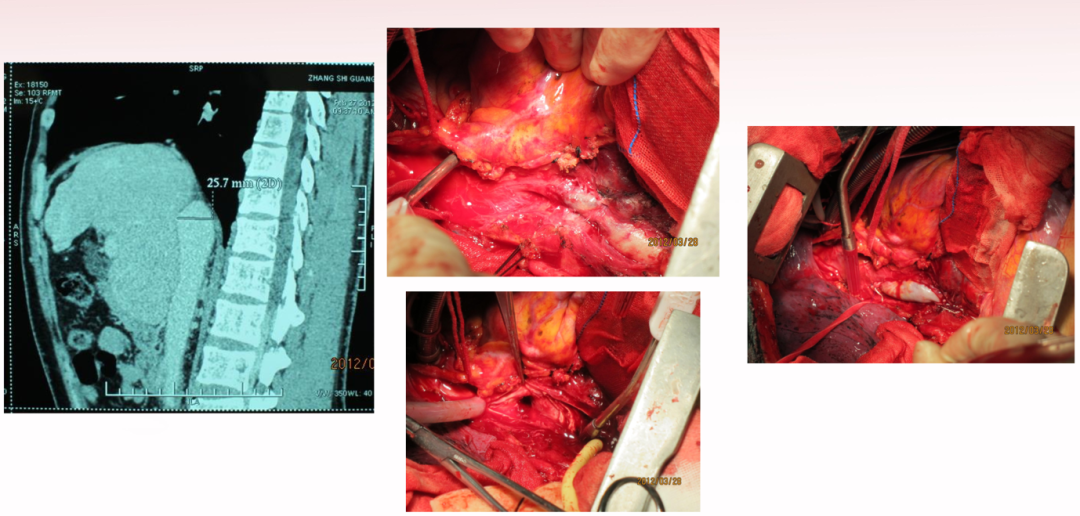

★ Case 1

肠房转流术

男性,26岁,因无明显原因出现腹胀纳差伴少尿一个月入院。

入院检查:强迫半卧位、巩膜黄染、腹部高度膨隆。双侧胸腔积液,大量腹水。

实验室检查:

总蛋白52.8g/L

白蛋白30.2g/L

谷丙转氨酶554u/L

谷草转氨酶378u/L

总胆红素74.9umol/L

直接胆红素18.51umol/L

尿素氮10.2mmol/L

低钠、低氯

肠房转流术后,现在随访14年